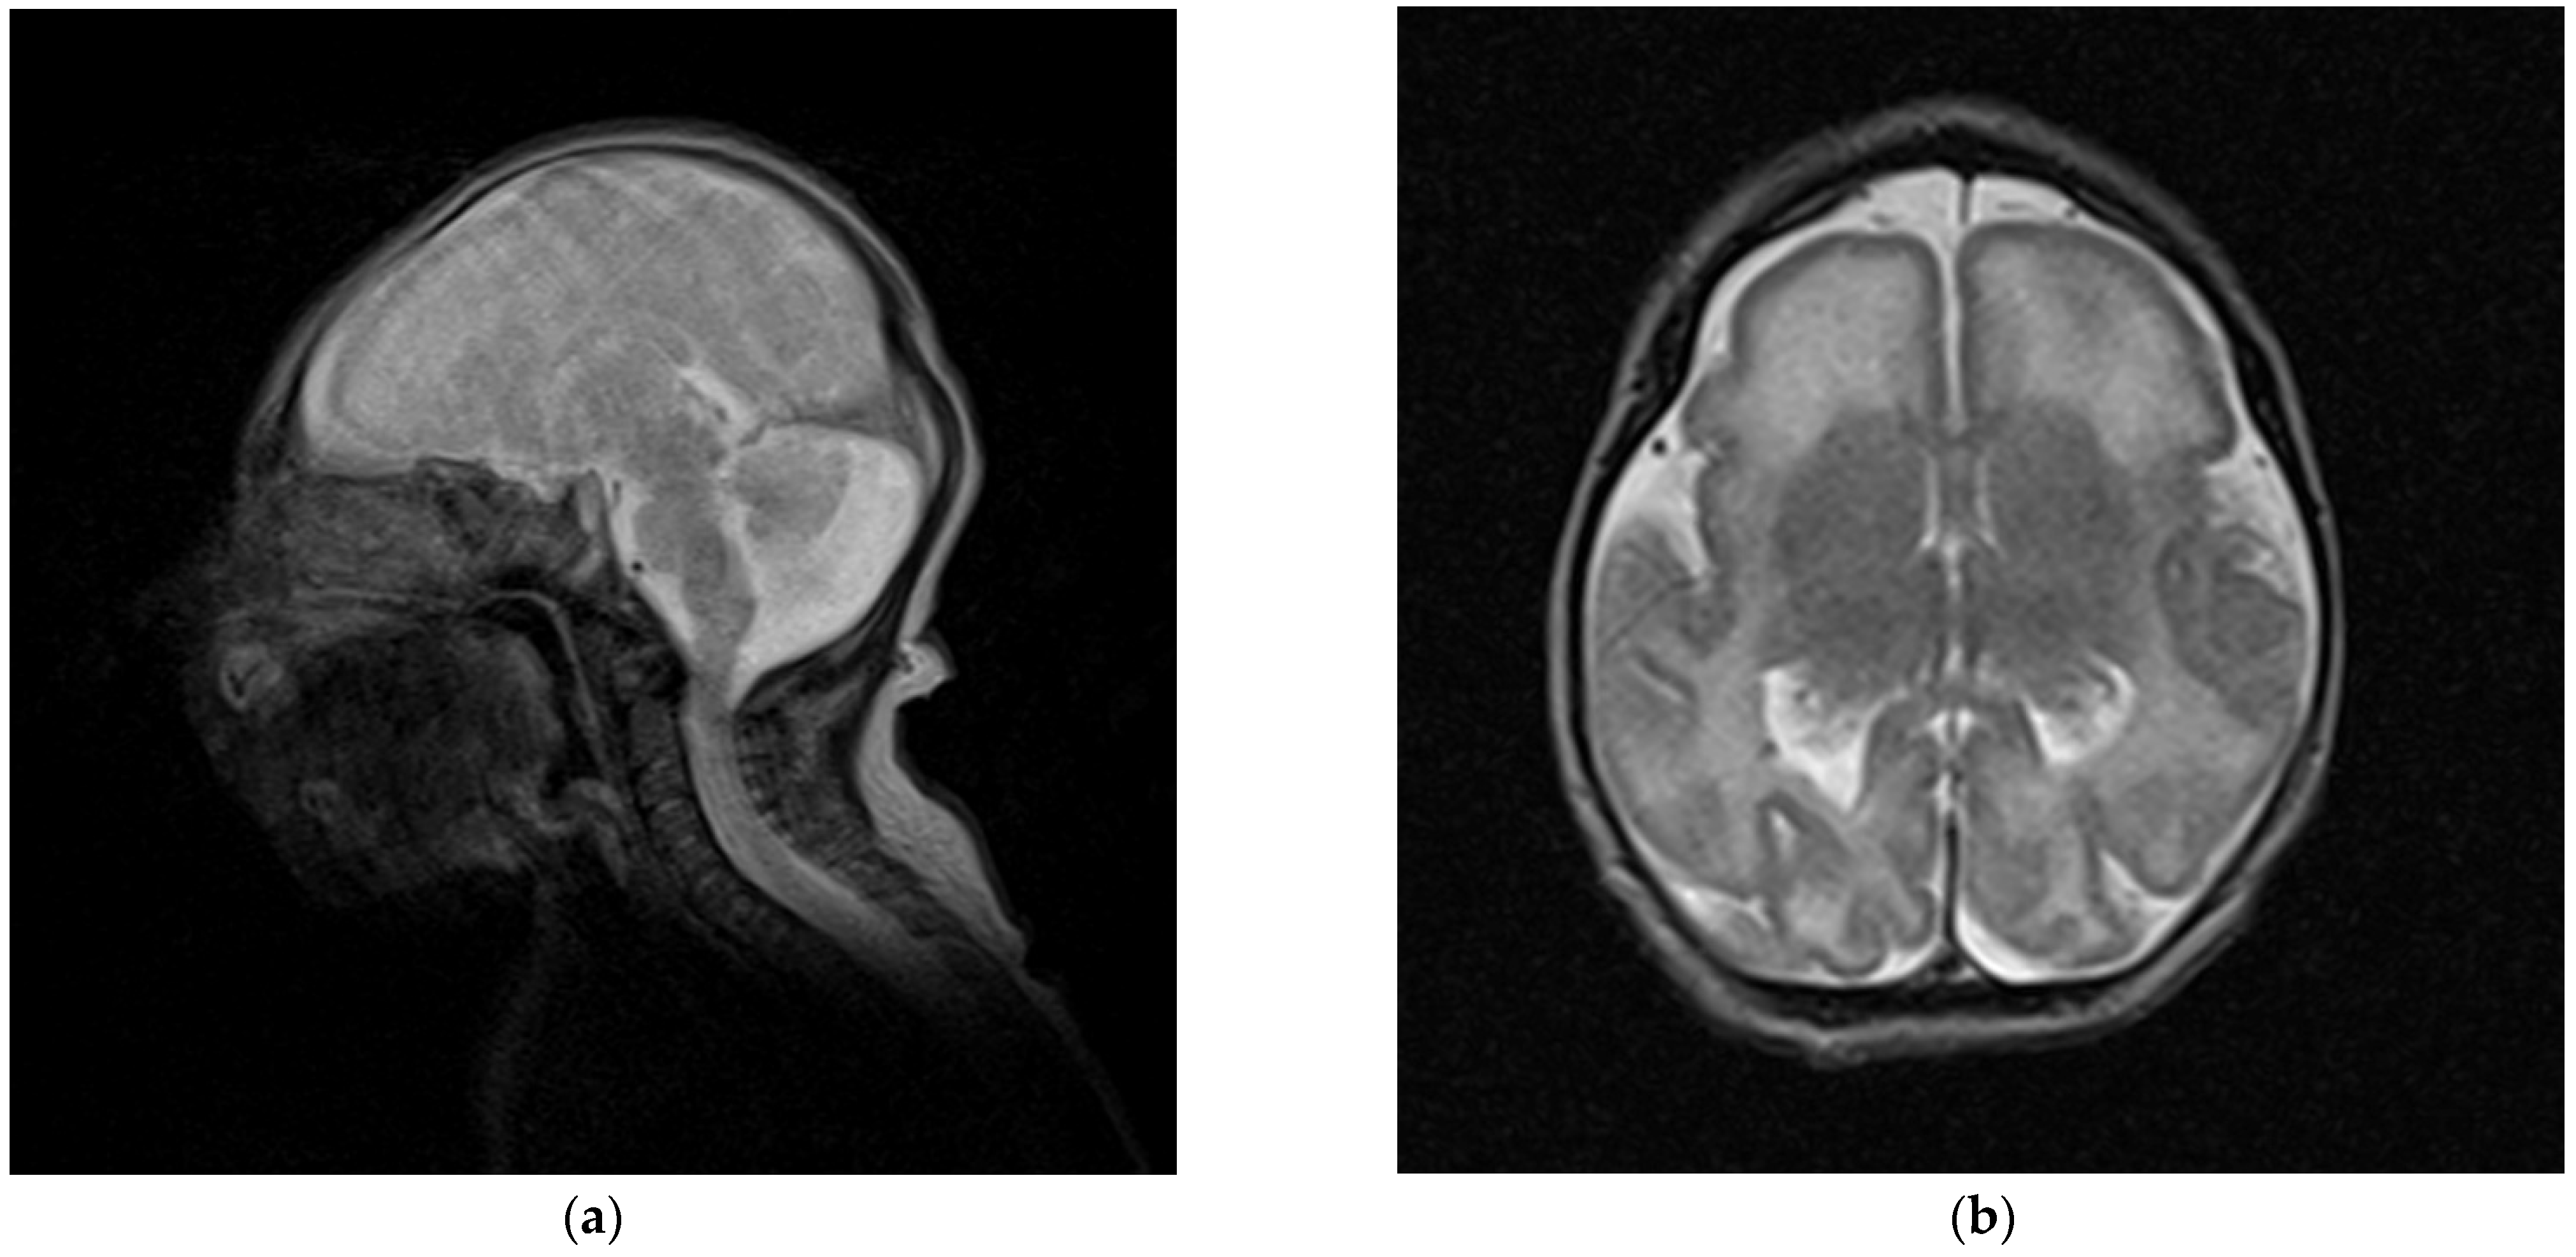

| This report | 1 | del ex 1−8 | −3.5 | −5 (10 y) | −2 | mild DD, profound ID (no language) | fronto-polar simplified gyral pattern, PNH, mild ventriculomegaly, enlarged posterior fossa | sloping forehead, highly arched eyebrow, exotropia, epicanthus, large ears; hyperactivity | Pakistani (northeast) |